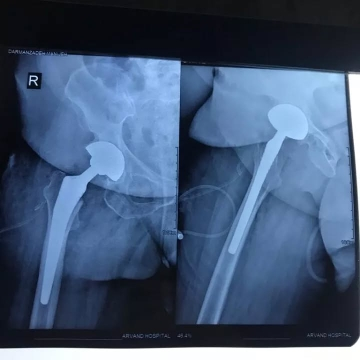

تعویض مفصل هیپ راست در خانم 64 ساله با استئوارتریت شدید هیپ راست ( آرتروز ) .

عکس های قبل و بعد از عمل خانم 64 ساله که استئوارتریت ( آرتروز ) شدید در مفصل هیپ راست با تغییرات مثبت در سی تی اسکن

با درد و محدودیت حرکتی شدید مفصل هیپ راست همراه با لنگش و کوتاهی در اندام تحتانی راست و ناتوانی در راه رفتن که تحت عمل جراحی تعویض مفصل هیپ راست از نوع دوال موبیلیتی آرتروپلاستی قرار گرفتند .